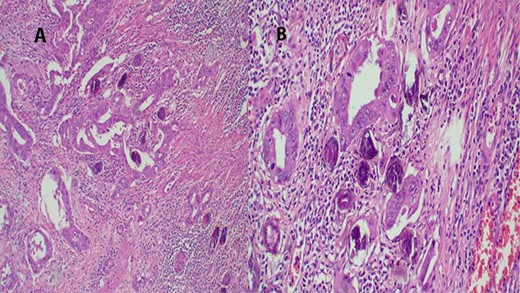

The report revealed a segment of colon with low-grade invasive adenocarcinoma (pT3NxM1) and Schistosoma eggs embedded in the tumor (Fig. 3).

(A) Histopathology of colon with adenocarcinoma associated with Schistosoma ova with poorly formed granulomatous inflammation, hematoxylin and eosin (H&E) ×20 magnification. (B) Adenocarcinoma and Schistosoma ova with dense lymphocytic infiltrates ×40 magnification.